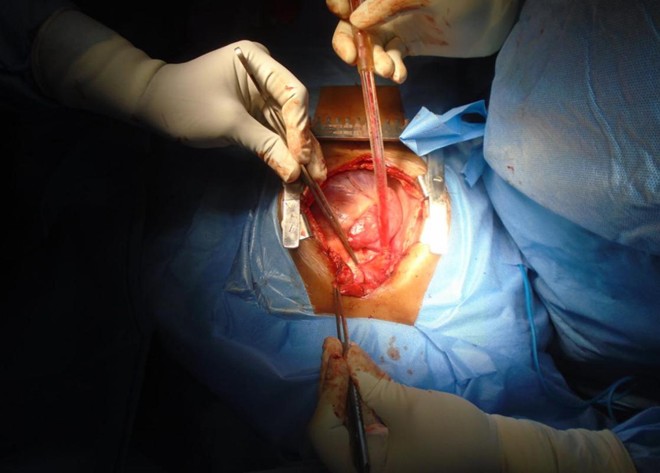

Procedure Images

Chest opened by a median sternotomy, pericardial patch harvested. Aortic, innominate vein/ IVC cannulation done. Antegrade DelNido plegia given. Cooled to 280C. Both cavae looped and snared. Vertical incision placed on the SVC extending across the SVC – RA junction into the RA. ASD closed with a pericardial patch rerouting the drainage of the right pulmonary veins into the LA. SVC closed with a pericardial patch using 5-0 Prolene sutures. Patient re-warmed. Weaned off CPB. Decannulation done. Sites reinforced. Patient in sinus rhythm. One atrial and one ventricular pacing wires placed. Chest closed with N6 steel wires after placing one right pleural and one mediastinal chest drains.